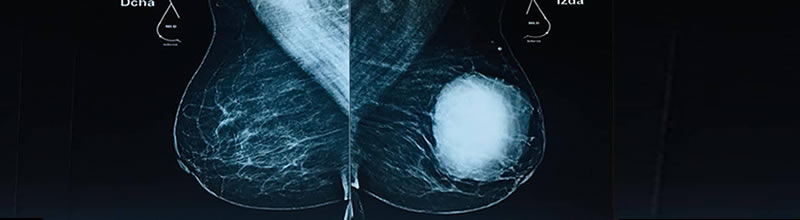

Nuestra misión es identificar el Cáncer de Mama en etapas tempranas con tratamiento eficiente, usando técnicas de vanguardia menos mutilantes y más conservadoras con reconstrucción inmediata.

Ultrasonido de mama de alta resolución con Doppler Color más Elastografía.